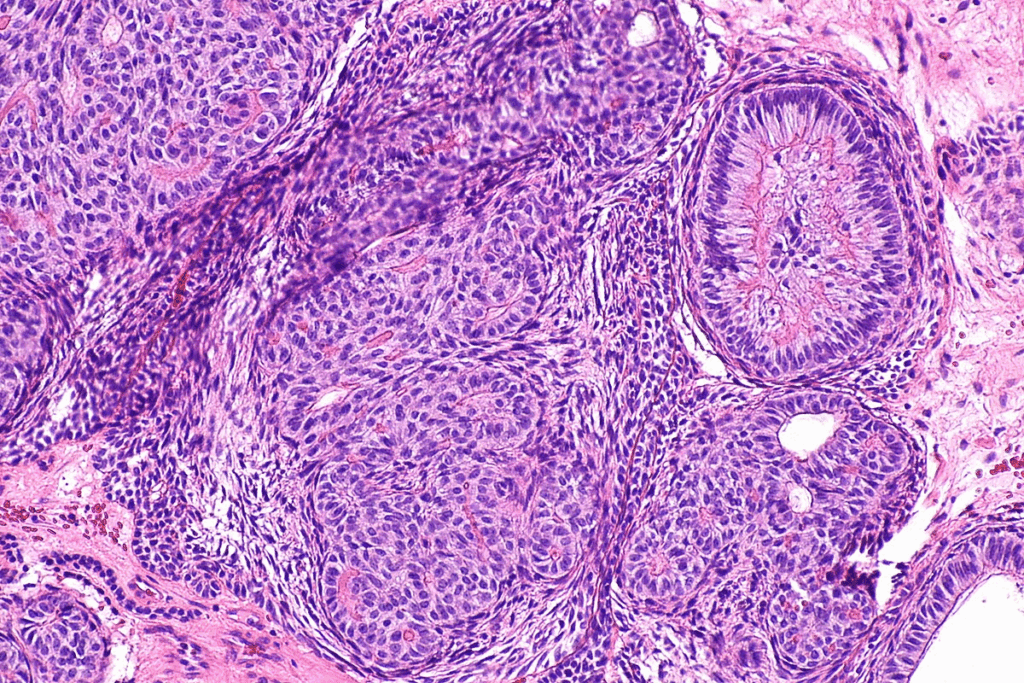

Different Types of Bladder Cancer

Bladder cancer is divided into several types based on where the cancer starts. The most common type is urothelial carcinoma, also known as transitional cell carcinoma. It starts in the urothelial cells lining the bladder. Other types, like squamous cell carcinoma and adenocarcinoma, affect different cells.

Grading of Bladder Cancer Tumors

Bladder cancer tumors are also graded based on how much they look like normal cells. The grade shows how fast the cancer is likely to grow and spread. Tumors are usually classified as low grade or high grade. Low-grade tumors grow and spread slowly, while high-grade tumors are more aggressive.

Knowing the type, stage, and grade of bladder cancer is key. It helps doctors plan the best treatment. It also helps patients understand their chances of recovery.